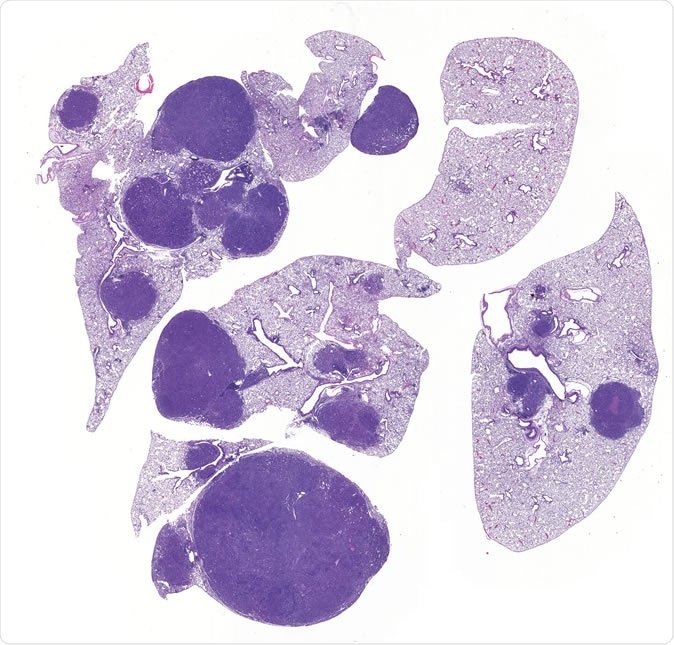

Image of lung cancer shows normal lung (light purple) and tumors (dark purple). Inactivation of SIK1 and SIK3 leads to tumor growth and inflammation, revealing for the first time that SIK kinases mediate key functions of LKB1 in preventing lung cancer. Click here for a high-resolution image. Credit: Salk Institute

The researchers used laboratory mice in the experiment and they analyzed how inactivation in the enzymes can affect tumor growth. Hence, the researchers were left with two kinases – SIK1 and SIK3. SIK1 had the greatest effect in stopping tumor growth. But, when SIK1 was inactivated, the rate of tumor growth heightened. Meanwhile, SIK3 has also been found to affect tumor growth. In fact, when it was inactivated, the tumor grew and proliferated more aggressively.

LKB1 also plays a pivotal role in inflammation suppression in cells. The researchers found that the two kinases were particularly stopping cellular inflammation when there are lung cancer cells. The researchers concluded that when LKB1 or the two kinases are mutated in tumors, there is increased inflammation, promoting cancer cell proliferation and tumor growth.